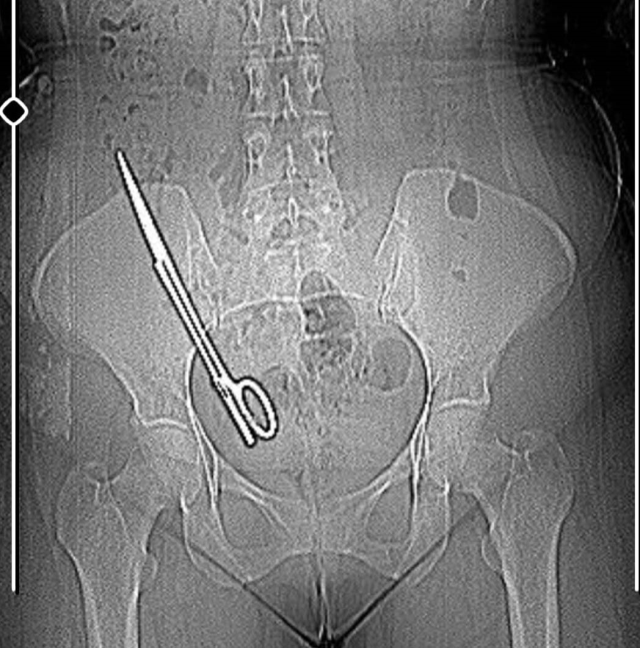

Kahramanmaraş'ta baş ağrısı şikayetiyle hastaneye giden Fatma Kala'nın karnında 16 santimetre uzunluğunda ameliyat makası tespit edildi.

Kent merkezinde yaşayan 2 çocuk annesi Fatma Kala, baş ağrısı şikayetiyle hastaneye gitti. Muayene sonrası Kala, MR bölümüne sevk edildi. Fatma Kala, MR'a girmeye hazırlanırken görevlilere, daha önce küçük çocuğuna MR çektirmek için birçok defa MR odasına girdiğini ve her defasında sağ tarafından çekme olduğunu söyledi. Daha önce bir operasyon geçirip geçirmediğinin sorulması üzerine Kala, 7 yıl önce özel bir hastanede kist ameliyatı olduğunu belirtti. Bunun üzerine Fatma Kala, ameliyatı olduğu doktora yönlendirildi. Kala, kendisini ameliyat eden Kadın Hastalıkları ve Doğum Uzmanı Doktor Koray Ş.'ye gidip muayene oldu, röntgen çekildi. İddiaya göre; Koray Ş., 7 yıl önceki ameliyattan dolayı bir komplikasyon oluştuğunu ve acilen ameliyat etmesi gerektiğini söyledi. Doktorun tavırlarından şüphelenen Fatma Kala, ameliyat olmayı reddedip KSÜ Sağlık Uygulama ve Araştırma Hastanesi'ne gitti. Burada yapılan tetkiklerde Kala'nın karnında 16 santimetre uzunluğunda makas olduğu tespit edildi. Ameliyatla karnındaki makas çıkarılıp salığına kavuşan Fatma Kala, hastaneden çıktıktan sonra avukatı aracılığıyla 7 yıl önce ameliyatı gerçekleştiren doktor Koray Ş. hakkında Kahramanmaraş Cumhuriyet Başsavcılığı'na suç duyurusunda bulundu.

Karnında makas varken küçük çocuğu ile birçok defa MR odasına girdiğini belirten Kala, "Bundan 7 yıl önce özel bir hastanede ameliyat oldum. O günün gecesinde tekrar iç kanama geçiriyorum ve ikinci ameliyatımı oluyorum. Bu ameliyatta maalesef ameliyat olan bölgemde ameliyat makası unutuyorlar ve biz bunu 7 sonra öğreniyoruz. Baş ağrısından dolayı hastaneye gittik. Hastanede doktorumuz MR'a girmem gerektiğini söyledi. Ben MR teknisyenine daha önce çocukla beraber MR odasına girdiğimde benim sağ tarafımda çekme olduğunu söyledim. Teknisyen bana 'Bu şekilde seni MR'a alamam, çok tehlikeli. Acilen ameliyat olduğun doktoru bul' dedi. Doktorumuz bizi hemen röntgene aldı. Röntgende bir yabancı cisim görmüş ama bize söylemedi, 'Daha önceki ameliyatından dolayı bir komplikasyon oluşmuş. Seni ameliyat edip dedi o komplikasyonu ortadan kaldırmam gerekiyor' dedi. Biz doktorun telaşlı tavrından şüphelendik. Eşimle birlikte tıp fakültesine gittik. Oradaki acil doktorlarına başımızdan geçen olayı anlattık. Onlar beni röntgene soktu. Oradan ilaçlı tomografiye girince daha önceki ameliyatımda bırakılan makas orada görüldü. Genel cerrahi bölümünde bu makas çıkarıldı' diye konuştu.